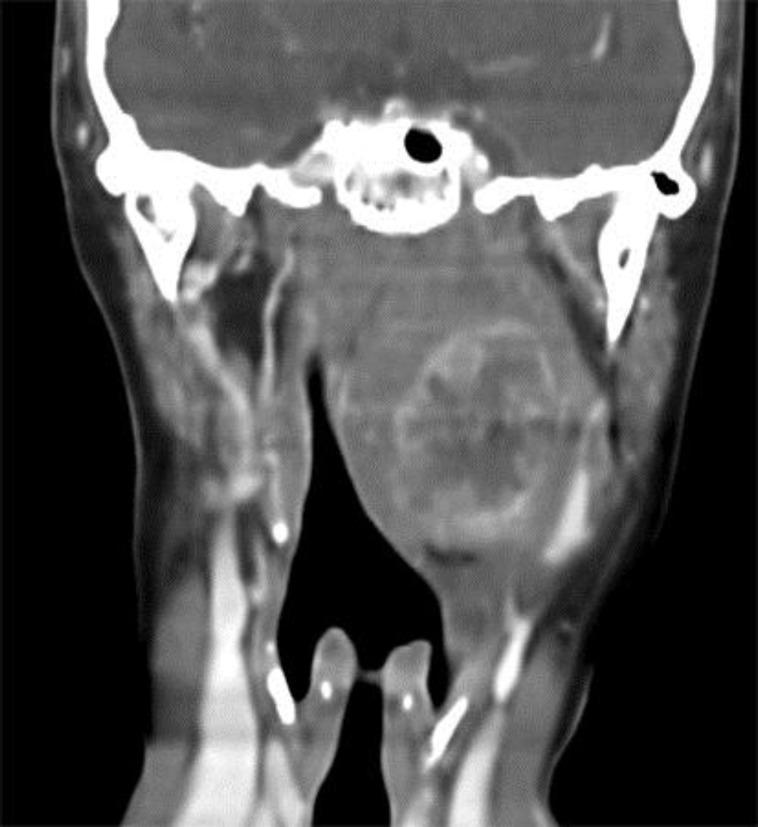

We report on a patient who presented to the Ear, Nose and Throat (ENT) clinic with swelling of the neck, dysphagia, headache, dyspnea and stridor. Imaging studies revealed an expansive heterogeneous process to the left retropharyngeal region. The mass was ovoid in shape, displaying moderate enhancement after intravenous contrast administration. Subsequently, a biopsy revealed the presence of undifferentiated sarcoma. The patient was treated with chemotherapy followed by radiation therapy, but follow-up exams at 6 months posttreatment revealed that while the tumor was stable, it persisted. Consequently, the patient was enrolled in a palliative care and pain control program and is currently being followed.

摘要

我们报告了一名患者,该患者因颈部肿胀、吞咽困难、头痛、呼吸困难和喘鸣而就诊于耳鼻喉科诊所。影像学检查显示左咽后区有一个膨胀性的异质性病变。肿块呈椭圆形,静脉注射造影剂后显示中度强化。随后,活检显示存在未分化肉瘤。该患者接受了化疗,随后进行了放射治疗,但治疗后6个月的随访检查显示,虽然肿瘤稳定,但仍然存在。因此,该患者参加了姑息治疗和疼痛控制项目,目前正在接受随访。